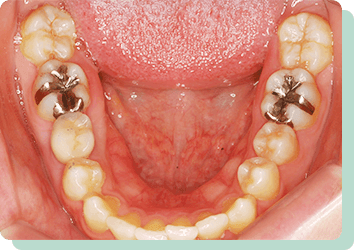

向かって左の歯は、根を支える骨の状態が悪く、残せるかどうか分からない位の歯でした。入れ歯やブリッジでの対応は難しく、右側にインプラントを入れてしっかりと咬合させることにより左の歯への負担を減らすことができました。結果10年以上経過した現在も問題なく機能しています。

リスク:疼痛・咬合時痛・冷水痛・出血・インプラント手術による歯ぐきなどの損傷・インプラント周囲炎など

費用:インプラント治療1本あたり440,000円